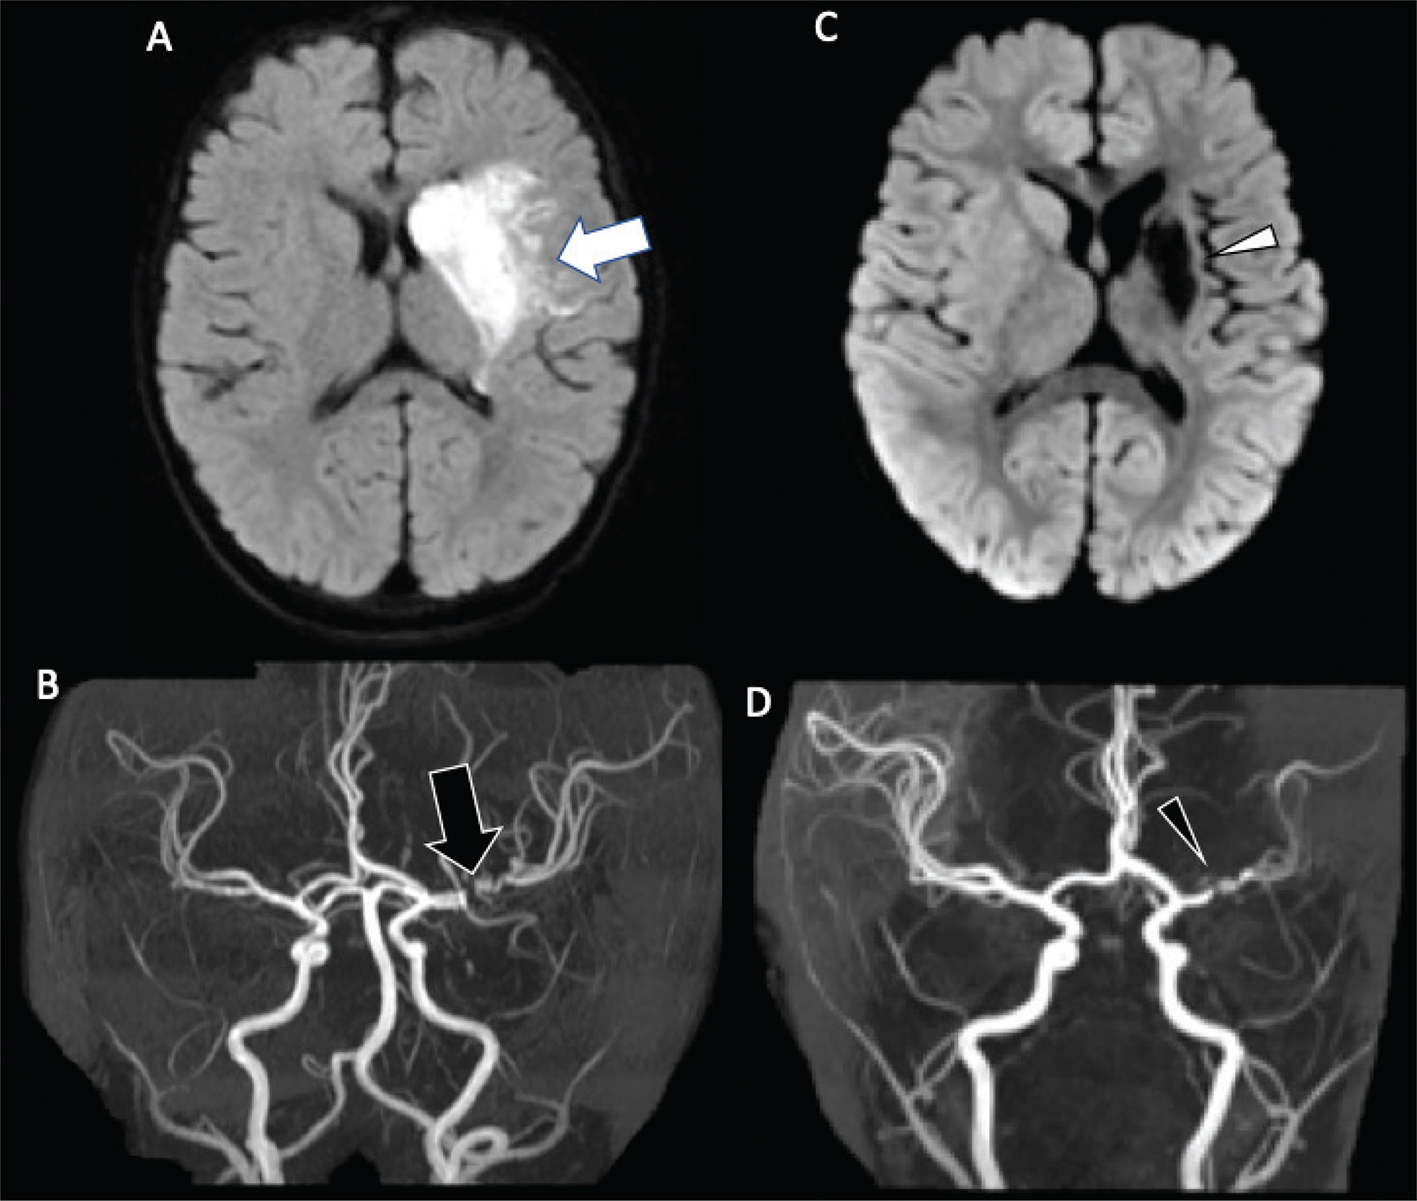

Fig 1

Figure 1. A six-month-old male who presented with acute right hemiparesis. DWI (A) demonstrates acute infarct in the left basal ganglia and deep white matter (white arrow). MRA (B) shows severe stenosis of the left M1 middle cerebral artery segment (black arrow). Follow-up 4 months later, demonstrates evolution of the infarct, now with encephalomalacia and gliosis without new acute infarct (white arrowhead) (C). MRA at that times shows mild improvement but persistent MCA stenosis (black arrowhead) (D). Findings are most compatible with focal cerebral arteriopathy.

Fig 5

Figure 5. A 13-year-old previously healthy female who presented with new left-sided facial weakness. Diffusion weighted image (A) demonstrate acute infarcts in the right middle cerebral artery (MCA) territory (black arrows). Time-of-Flight MRA (B) shows stenosis of the proximal right M1 MCA segment (white arrowhead). Vessel wall imaging (C) demonstrates a cuff of enhancement at the stenosis (white arrow). Digital subtraction angiography (D) demonstrates a focal arterial irregularity and banding (black arrowhead) resulting in mild stenosis, compatible with focal arteriopathy of a likely inflammatory nature.